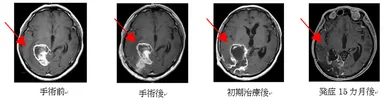

症例2 :56歳男性

主訴 :頭痛、半盲

現病歴 :2014年10月14日から頭痛出現。11月6日手術を施行。

病理は膠芽腫。放射線60Gy、テモダール(75mg/m2)投与。

ノニジュースを併用。

セカンドオピニオンで2015年2月12日駒込病院転院。

外来での経過:テモダール(75mg/m2)4週おきに投与し、

2016年1月20日まで再発なし。

その後の経過:手術にてはほとんど摘出できなかったが、

初期治療後ほぼ腫瘍は内部から消失。

発症24カ月後の現在再発はない。